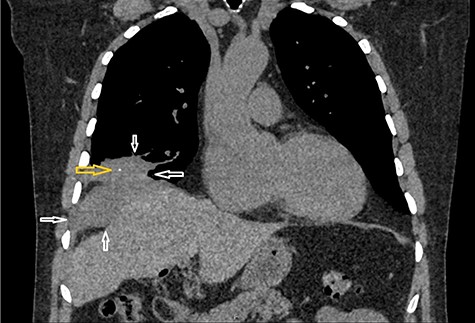

A 65-year-old gentleman with no comorbidities underwent elective laparoscopic cholecystectomy for symptomatic gallstones in 2013. His operation was complicated by intra-operative spillage of gallstones, which were retrieved. The patient remained well until 2017 when he developed a long-standing dry cough. Computed tomography (CT) scan chest showed a right lung base mass lesion with a large area of contact with diaphragmatic pleura, also abutting the right lobe of the liver. A small area of calcification was seen in the mass lesion thought to be part of the malignant process (Fig. 1).

CT scan chest coronal view: Figure demonstrates a mass lesion at the right lung base with an area of calcification. White arrows demonstrate the edges of the mass lesion. Yellow arrow denotes the area of calcification in the mass.